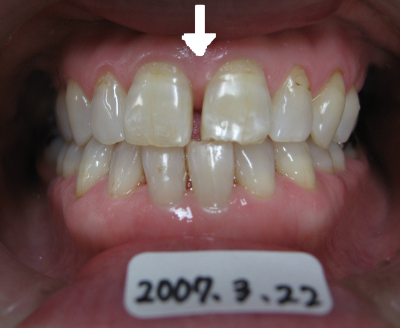

矢印の部分の隙間が気になる。

しかし歯は削りたくない。

歯と歯の間にプラスチックを流し込んで約10分で治療終了。

歯は一切削っていません。

2012年08月11日現在、変色もなく良好。